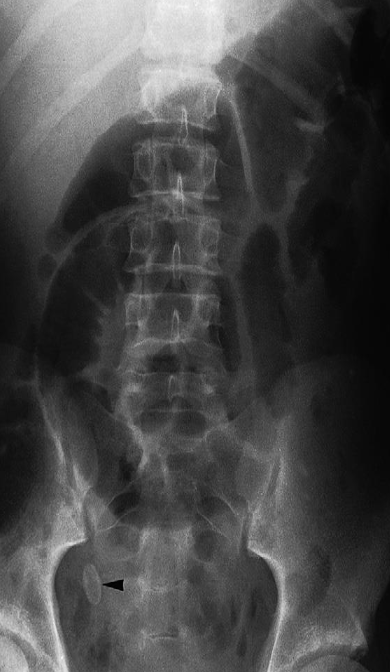

Imaging examination Plain X-ray

Findings or description The oval calcified shadow (arrowhead) is a faecolith in the appendix.

Sign Note the dilated loops of small bowel in the centre of the abdomen due to peritonitis – the so-called sentinel loops

Diagnosis Appendicolith